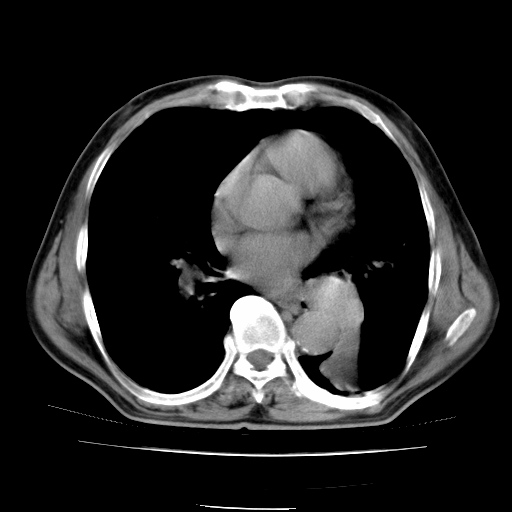

男,71岁,咳嗽,气喘10年,再发并咯血.胸片见气胸

考虑  左肺中心型肺癌伴阻塞性肺炎,肺不张,纵膈淋巴结肿大。慢支炎,肺气肿,左侧气胸肺压缩5%

左侧中央型肺癌伴纵膈淋巴结转移。

左肺中心型肺癌伴阻塞性肺炎,肺不张,纵膈淋巴结肿大

1)考虑左肺中心型肺癌伴阻塞性肺炎、左肺下叶肺不张、左侧肺气肿,纵膈淋巴结转移。2)左侧气胸(肺组织压缩约5%)。

左肺中心型肺癌伴阻塞性肺不张、肺气肿 。

1)考虑左肺中心型肺癌伴阻塞性肺炎、左肺下叶肺不张、左侧肺气肿,纵膈淋巴结转移。2)左侧气胸。